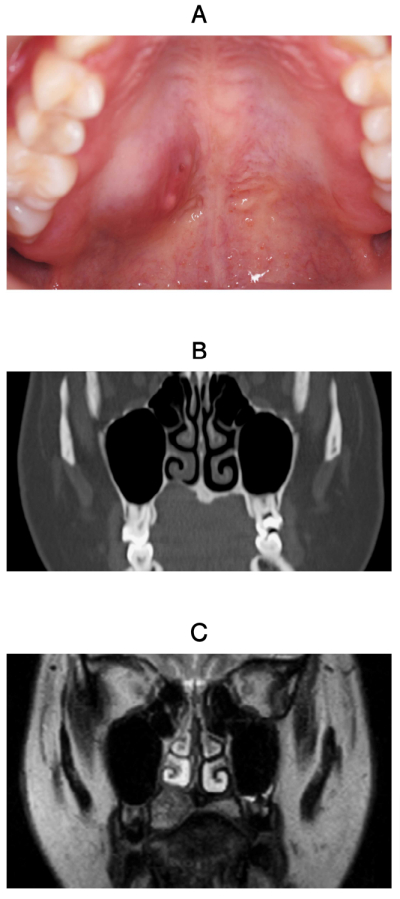

25歳の女性。右側口蓋部の無痛性腫脹を主訴として来院した。1年前から軽度の腫脹に気付いていたがそのままにしていたところ、最近徐々に増大したという。同部に波動や圧痛はない。初診時の口腔内写真、CT、MRI T2強調像及び生検時のH-E染色病理組織像を示す。